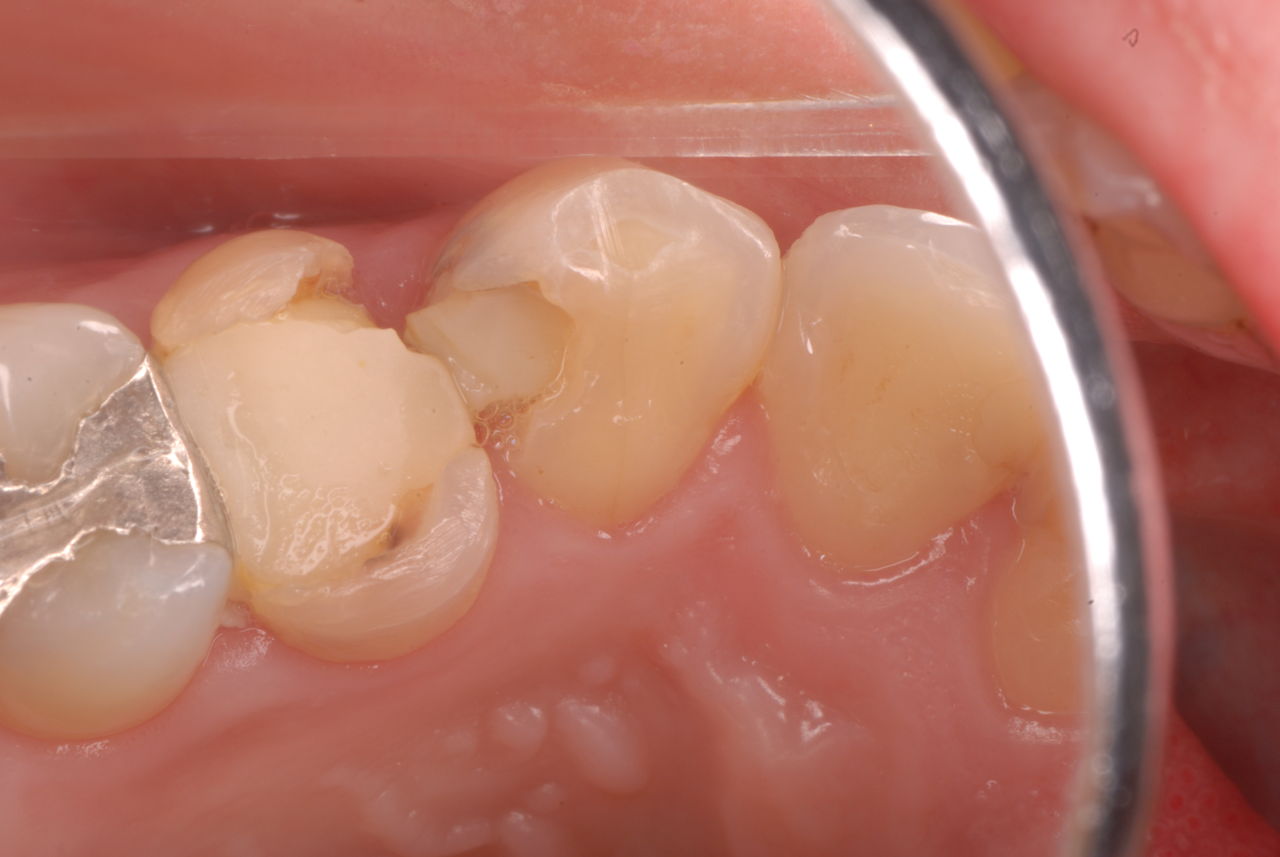

下記は患者に言われるままに血だらけでの不潔な状態で虫歯をとり埋めたようで全然適合していませんし、外れそうになっていました。

外したところです。中は虫歯のオンパレードでした。

適合が悪い銀歯が装着されていて更に虫歯の取残しにより歯髄炎症を起こして神経を取らざるをえなくなりました。神経を除去すれば痛みはなくなります。でもそれは死ぬことなのです。ほぼ寿命は半減したと考えるしかないのです。

まずは掃除の仕方を学ぶべきだったのです。環境をある程度良くしてから治療しないのでほぼ失敗に終わり、またハズレて虫歯により崩壊してしまうのです。